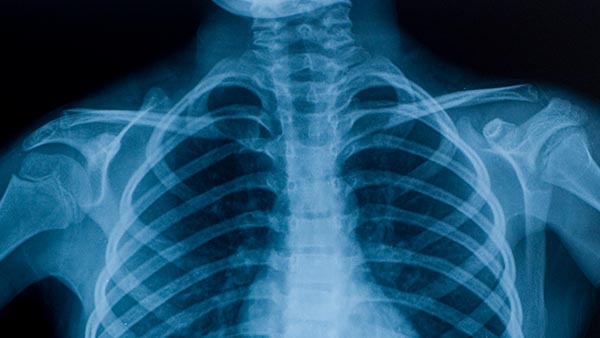

Dragon Medical Practice Edition 4.1 has over 60 medical specialties including Radiology.

This makes it highly accurate and effective for Radiologists.In this video demonstration Dragon Medical Practice Edition is dictating a Radiology sample script directly into Genie solutions via a remote connection. So if you're using Genie in a remotely hosted server you can have the confidence that Dragon Medical will work for you.